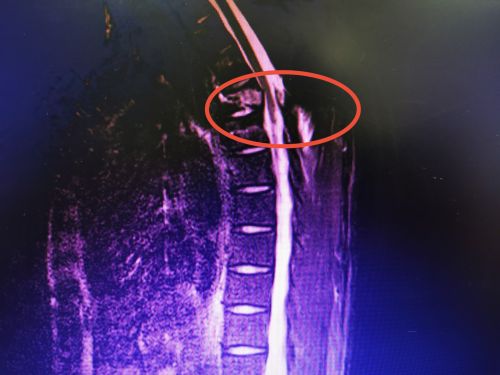

翁先生术前影像显示:胸4椎体及附件骨折伴骨髓水肿,继发骨性椎管狭窄、后方韧带复合体撕裂。

不要以为只有老年人运动协调能力退化不经摔,年轻人也不例外。株洲29岁的翁先生从3米高的杨梅树上坠落,胸背部着地,胸背呈持续性刺痛,急诊以“胸椎爆裂性骨折”收入省人民捷克论坛 脊柱外科。完善术前相关检查后,沈雄杰主任医师等为他在全麻下进行胸椎后路复位植骨内固定术。术后,患者生命体征平稳,四肢肌力正常,转入普通病房继续治疗。